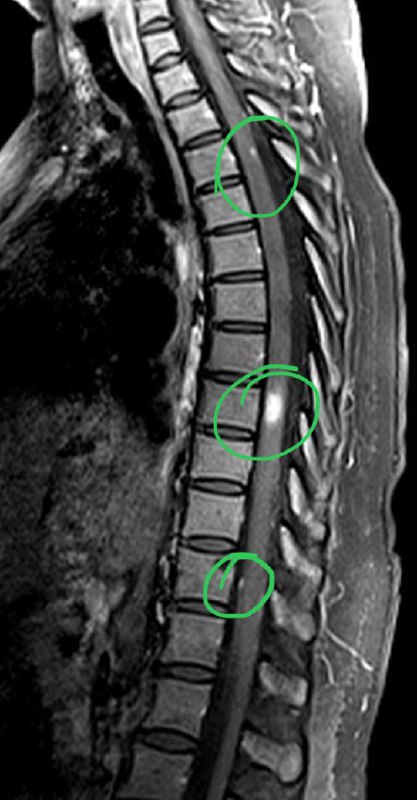

Анапластическая менингиома намета мозжечка справа с оболочечной спинальной диссеминацией у пациента 36 лет.